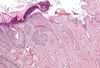

Tissue from a raven; what is the etiology?

Poxvirus

Pathogenesis (img)

Grain overload, rumenal acidosis, mucosal damage, opportunistic fungal infection, vasculitis, ischemia and mucosal ulceration